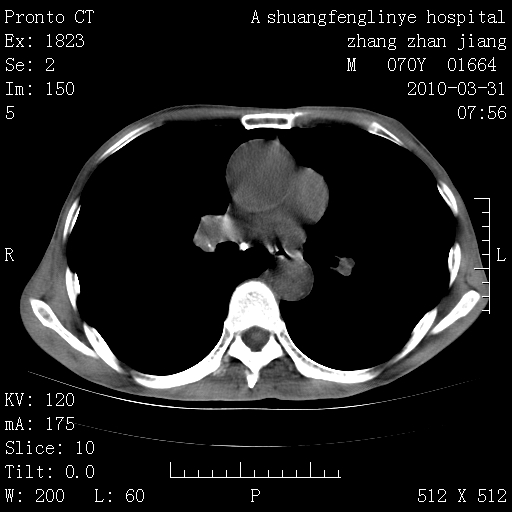

双上肺继发型tb并左上空洞形成,主动脉冠脉钙化。

支持:继发性肺结核伴空洞形成!建议纤支镜检查待出外周围型肺癌可能!

1)两肺上叶继发性肺结核并左肺上叶空洞形成。2)冠状动脉及主动脉钙化。